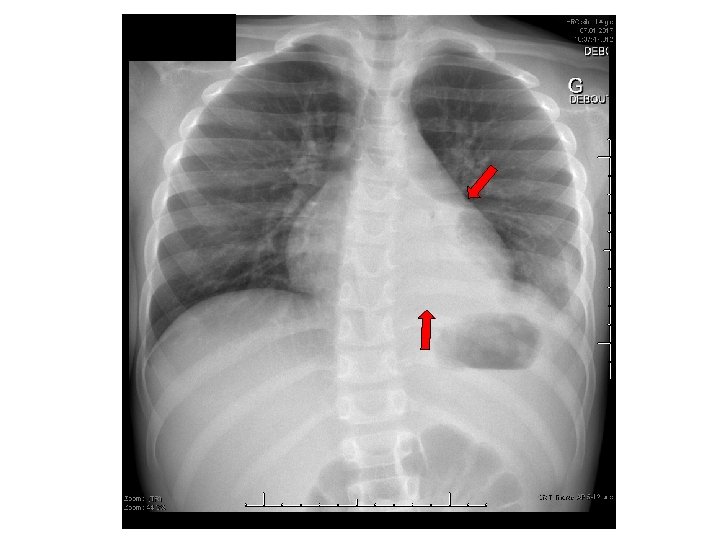

SCANNER THORACIQUE + ABDOMEN Masse médiastinale antérieure englobant les gros vaisseaux de taille 8 cm x 7. 5 cm x 7 cm, condensation atéléctasique, pas d'infiltrat, petite lame de pneumothorax gauche, foie, rate, pancréas sans particularité DD: lymphome le plus probable, thymome, tératome.

SCANNER THORACIQUE + ABDOMEN Masse médiastinale antérieure englobant les gros vaisseaux de taille 8 cm x 7. 5 cm x 7 cm, condensation atéléctasique, pas d'infiltrat, petite lame de pneumothorax gauche, foie, rate, pancréas sans particularité DD: LYMPHOME LE PLUS PROBABLE, THYMOME, TÉRATOME TF CHUV